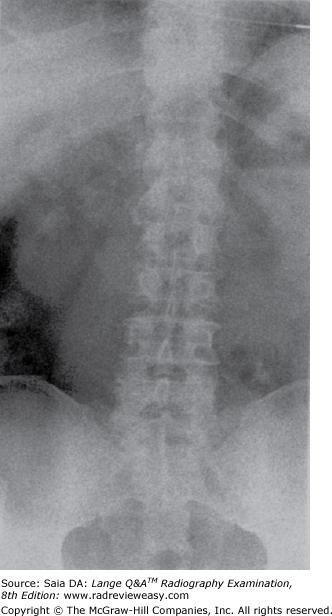

Which of the following statements is (are) true with respect to the radiograph shown in Figure 4–29?

- The image exhibits long-scale contrast.

- The image exhibits soft tissue fold.

- The image demonstrates motion blur.

A 1 and 2 only

B 1 and 3 only

C 2 and 3 only

D 1, 2, and 3

-The abdomen radiograph shown in the figure demonstrates motion blur. This can be seen particularly in the upper abdomen and in the bowel gas patterns. Motion obliterates spatial resolution. Patients who are in pain often are unable to cooperate as fully as patients who are not in pain. Careful positioning and patient instruction are helpful, but it remains useful to use the shortest exposure time possible. The radiograph also demonstrates good long-scale contrast that enables visualization of many tissue densities. The dark horizontal line across the abdomen is a soft tissue fold accentuated by a taut elastic underwear waist-band.